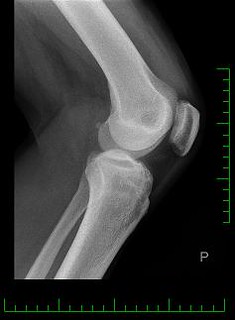

3. 콘드로이친 1200mg 효능 골관절염 진행 완화

게다가, 콘드로이친은 관절염의 진행을 늦추는 것으로 발표되었습니다. 관절염의 특징으로, 연골의 퇴화는 시간이 지남에 따라 관절 손상과 악화로 이어지게 되는데 연구에 따르면 콘드로이친은 연골을 보호하고 보존하는 데 도움을 줄 수 있으며, 잠재적으로 퇴행 과정을 늦추고 관절 건강을 유지할 수 있습니다.